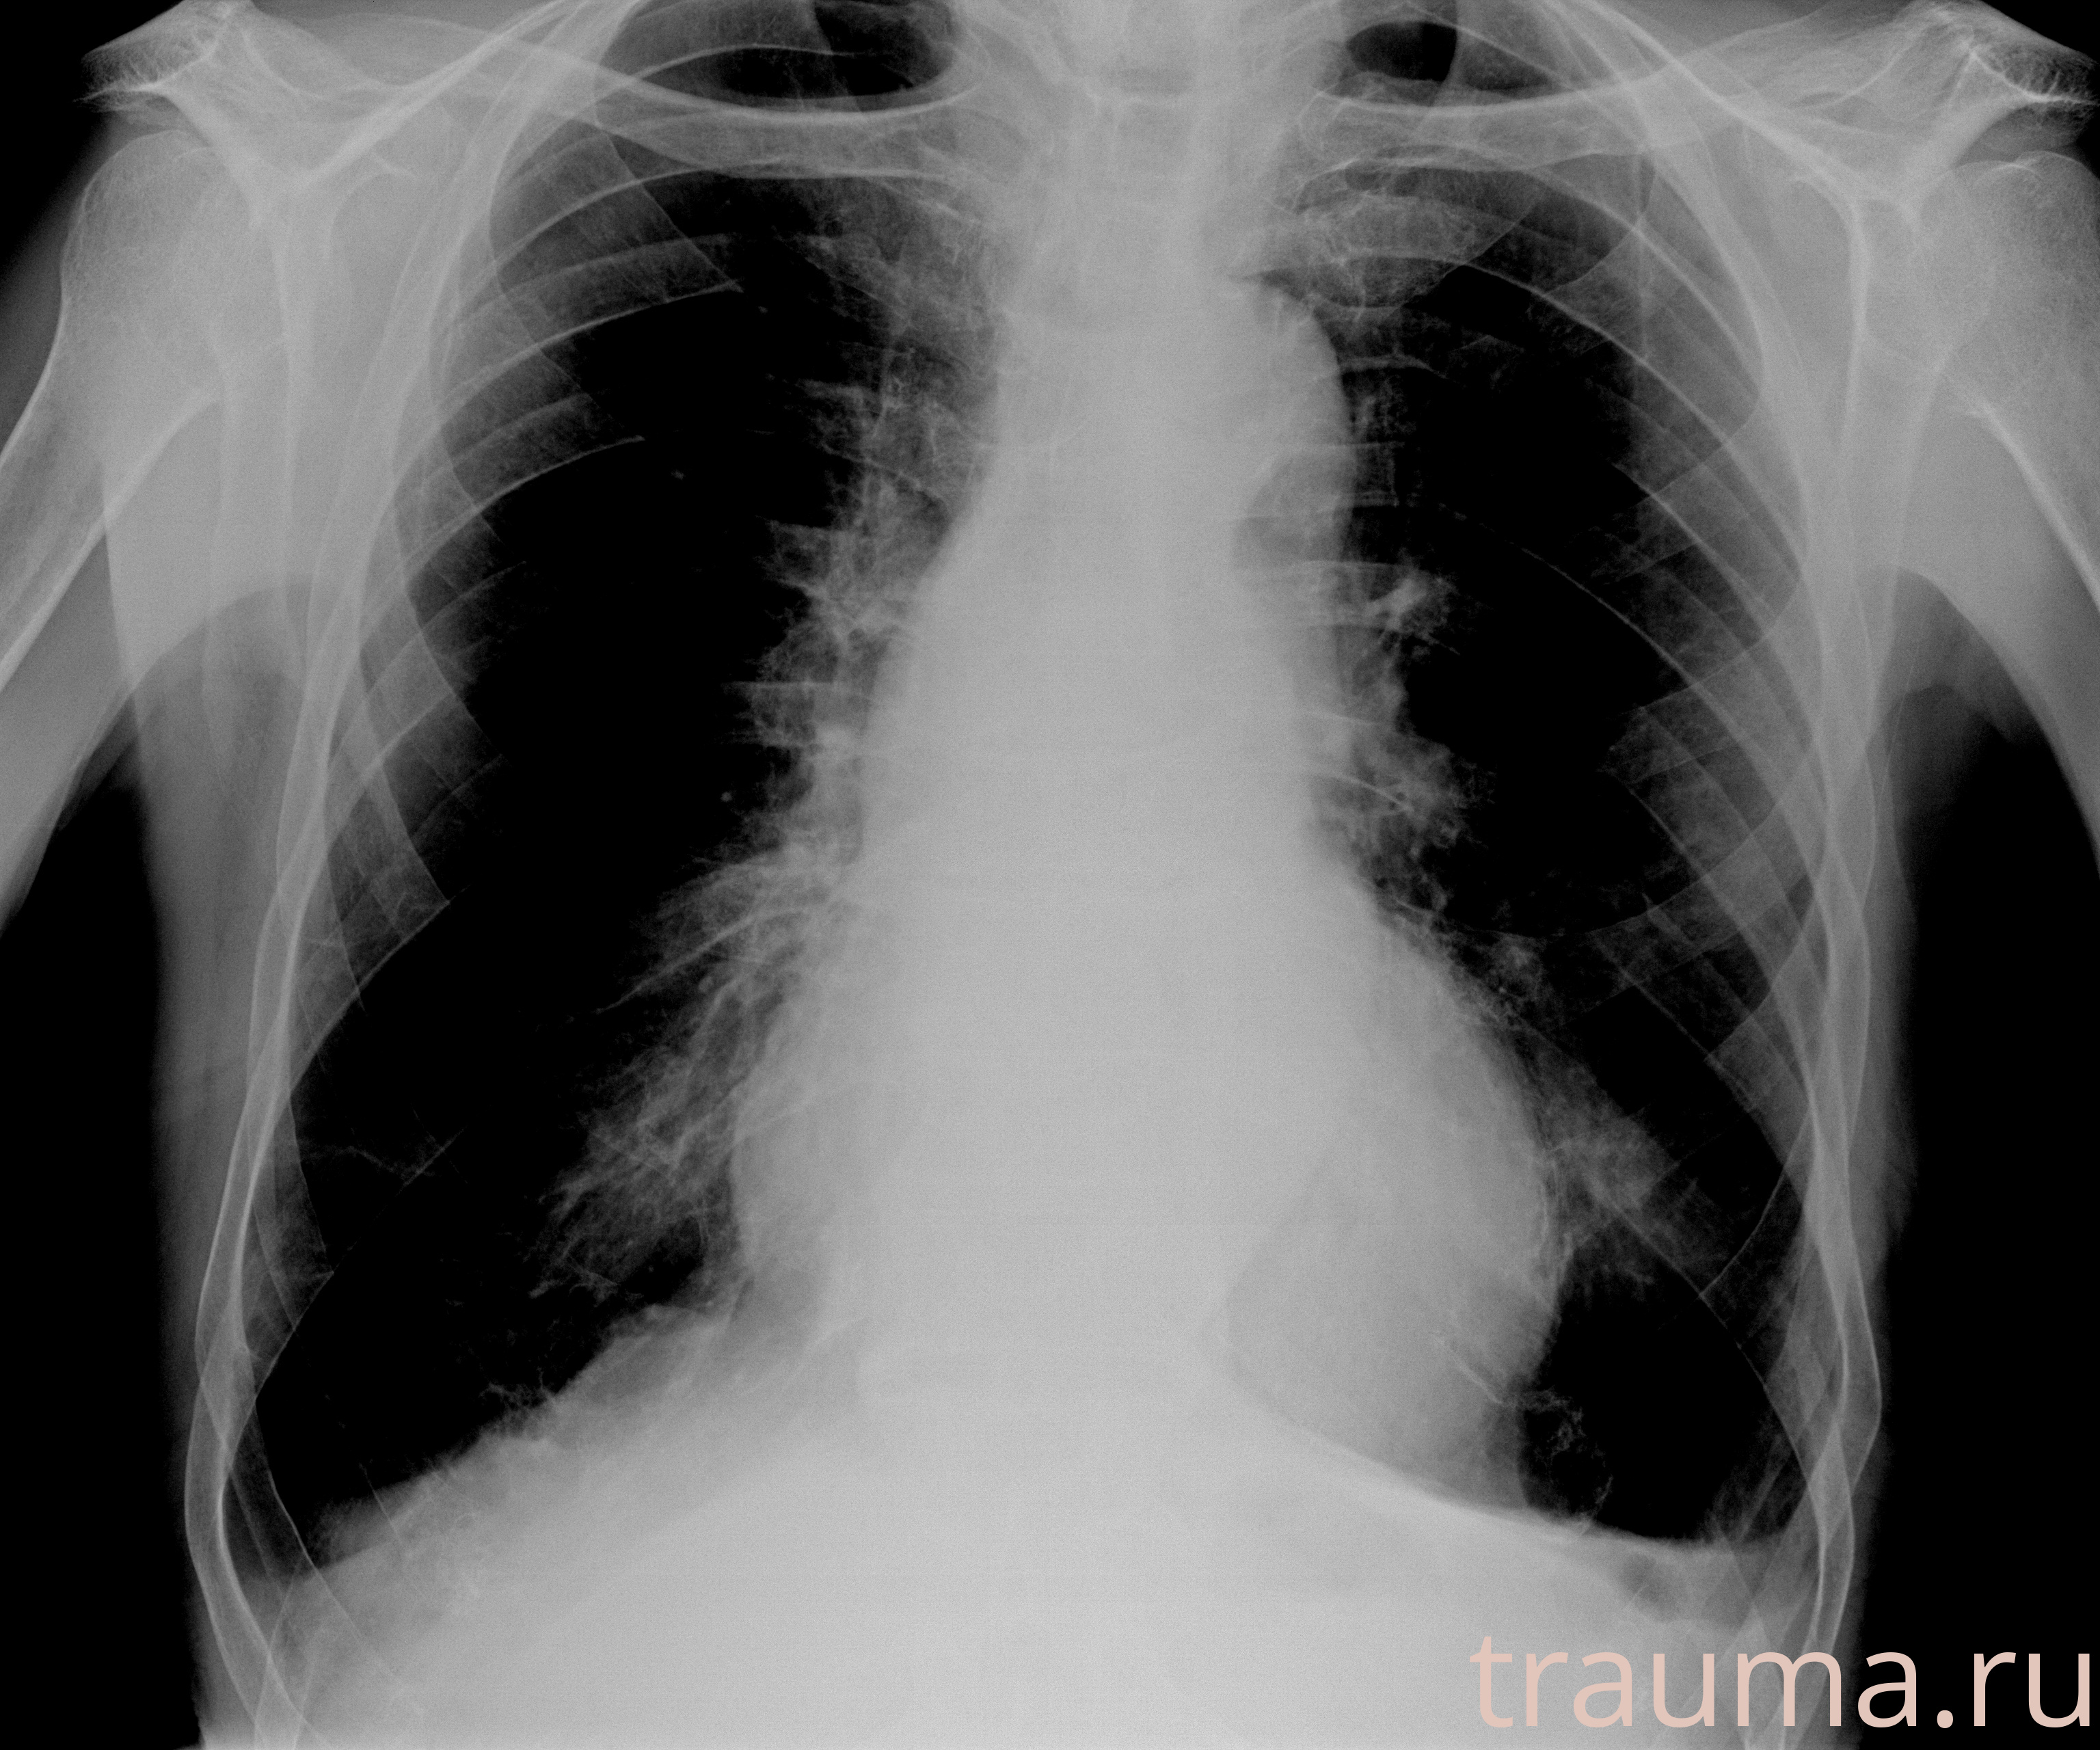

Рентгенограммы

Рентген на дому: по вашему адресу приезжает врач-рентгенолог, травматолог-ортопед с мобильным рентгеновским аппаратом, проводит диагностику травмы или заболевания, делает необходимые рентгенограммы, дает рекомендации по дальнейшему лечению. Получить качественные снимки в домашних условиях возможно благодаря уникальной методике, разработанной МосРентген Центром для института  Склифосовского